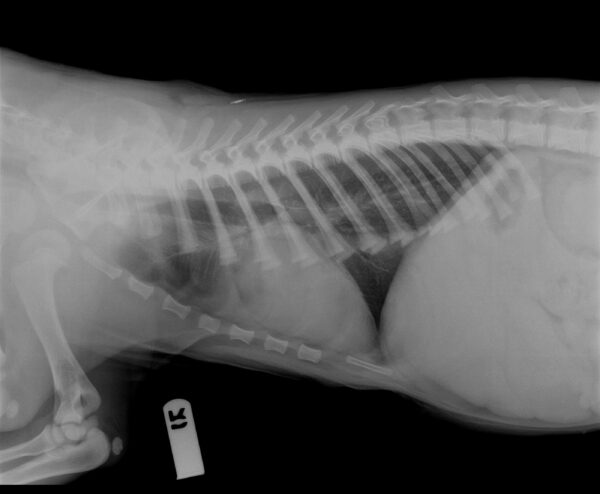

Last week the cubs received their final vaccines as kittens until they turn a year old. X-rays were taken to get an overall perspective of their health and these tigers are as perfect as they seem. From their teeth and gums, eyes, ears and

paws, these little tigers are in top shape! During their wellness visit, the veterinary staff also took the opportunity to get some colorful paw prints of the cubs that may be available for purchase soon.